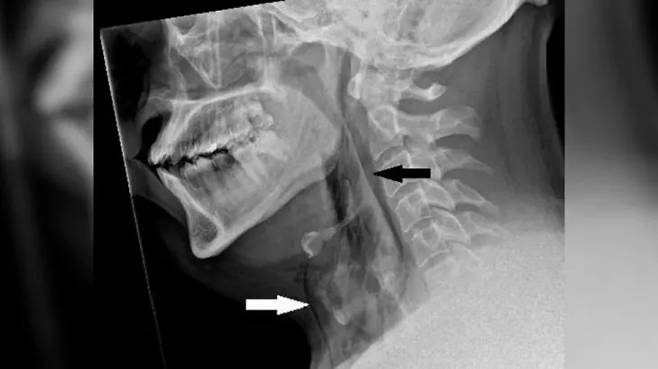

이로 인해 심한 통증이 발생했고, 응급실을 방문한 그는 X-ray 촬영 결과, 폐기종의 징후가 발견됐다.

CT 스캔에서는 목의 세 번째와 네 번째 뼈 사이에 기도가 찢어진 흔적이 보였으며, 이로 인해 공기가 목의 조직과 폐 사이로 빠져나갔다.

기도에 생긴 구멍의 크기는 지름 2㎜로, 이로 인해 급격히 증가한 압력이 기도에 영향을 미친 것으로 의료진은 진단했다.